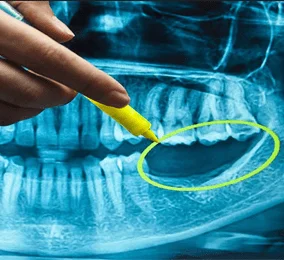

Tiêu xương hàm

Trồng Implant sớm để ngăn ngừa hiện tượng tiêu xương hàm. Khi trồng răng, áp lực được duy trì thường xuyên, xương hàm sẽ không bị ảnh hưởng hay tiêu biến.